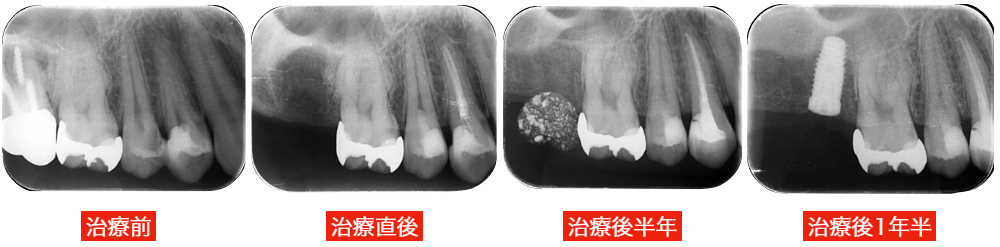

1か月〜半年の間隔で状態を確認します。

痛み・しみる症状・レントゲン所見をチェックします。

必要なら追加処置を検討します。

文献的には約70〜90%程度とされ、材料や適応判断の進歩により結果は向上しています。

絶対に神経を残せるわけではありませんが、従来なら神経を取る事になっていた症例でも温存できるケースは増えています。